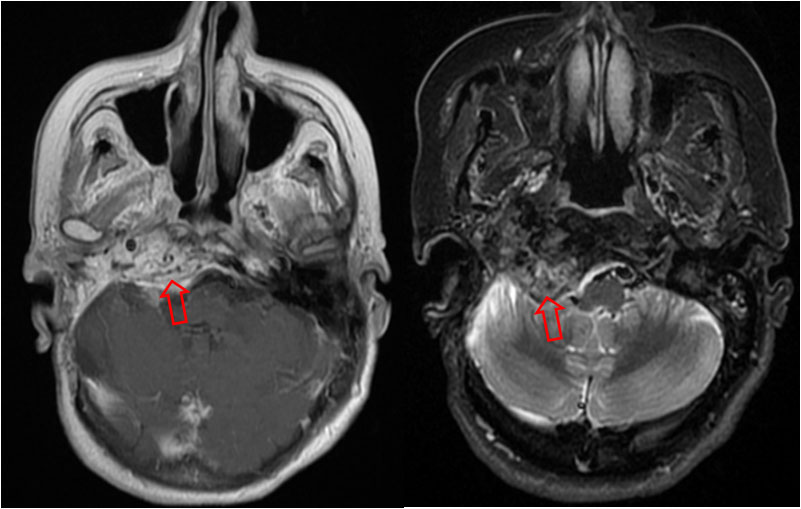

SIGNO DEL CEREBELO BLANCO o SIGNO INVERSO

Las imágenes muestran el cerebelo blanco. Se trataba de una niña que sufrió ahogamiento en una piscina.

Es un signo de edema cerebral difuso en la TC, también llamado signo del cerebelo denso o signo inverso (reversal sign). El cerebro muestra una disminución difusa de la densidad y una pérdida de la diferenciación entre la sustancia gris y la sustancia blanca, mientras que, el cerebelo -en cambio- está relativamente hiperdenso con respecto a los hemisferios cerebrales. También quedan respetados los tálamos y el tronco cerebral.

Este signo se ha descrito en cuadros de daño cerebral hipóxico como asfixia neonatal, ahogamiento, status epiléptico, meningitis bacteriana y encefalitis. Indica un daño cerebral irreversible con pésimo pronóstico.

No se conoce con exactitud la fisiopatología pero se postula que se produce por redistribución del flujo inracraneal con preservación de la circulación posterior y edema cerebral secundario.

La imagen corresponde a una niña que sufrió un ahogamiento en una piscina.